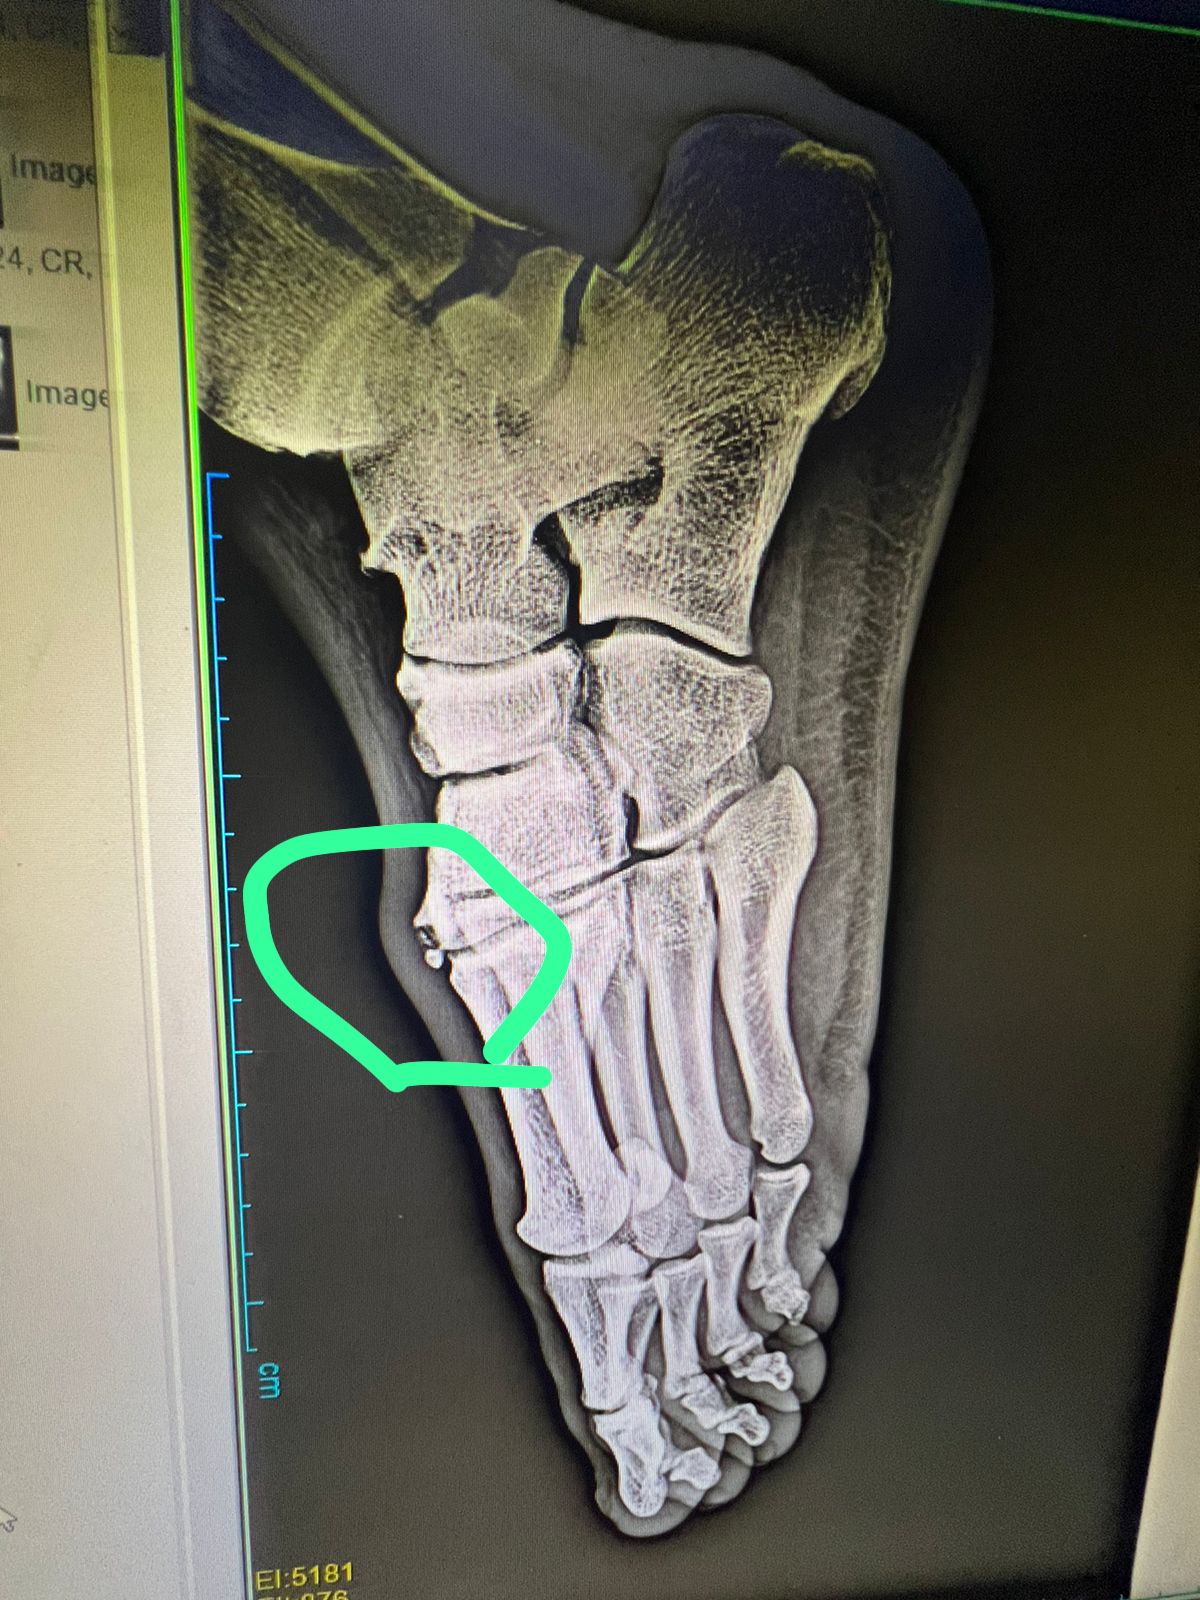

خاض القمة مصابًا.. الأشعة تكشف إصابة أحمد فتوح بكسر في وجه القدم | صورة

خضع أحمد فتوح، لاعب الفريق الأول لكرة القدم بنادي الزمالك، لآشعة على القدم بعد إصابته في مباراة كأس السوبر المصري أمام الأهلي.

وعلم القاهرة 24 أن الآشعة أوضحت إصابة أحمد فتوح بكسر بسيط في عظمة وجه القدم، وسيقوم اللاعب بوضع قدمه في الجبس بداية من الغد ولمدة أسبوعين.

وظهرت تداعيات إصابة أحمد فتوح عقب مباراة الزمالك وسيراميكا كليوباترا، بعدما اشتكى اللاعب آلاما في وجه القدم، واضطر الجهاز الفني لمشاركة اللاعب لجاهزيته في مباراة القمة، لتتفاقم الأزمة ويخرج مصابًا من مواجهة الأهلي.

وتأكد غياب أحمد فتوح عن مباراة الزمالك المقبلة أمام إنبي والمقرر لها يوم الأربعاء المقبل في تمام السابعة مساءً، في مباراة من الجولة الرابعة لبطولة الدوري الممتاز.